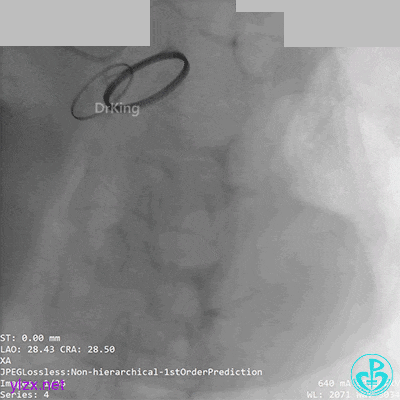

05 急诊冠脉造影

前降支血流3级,前降支近段、对角支开口大量血栓,回旋支开口闭塞。